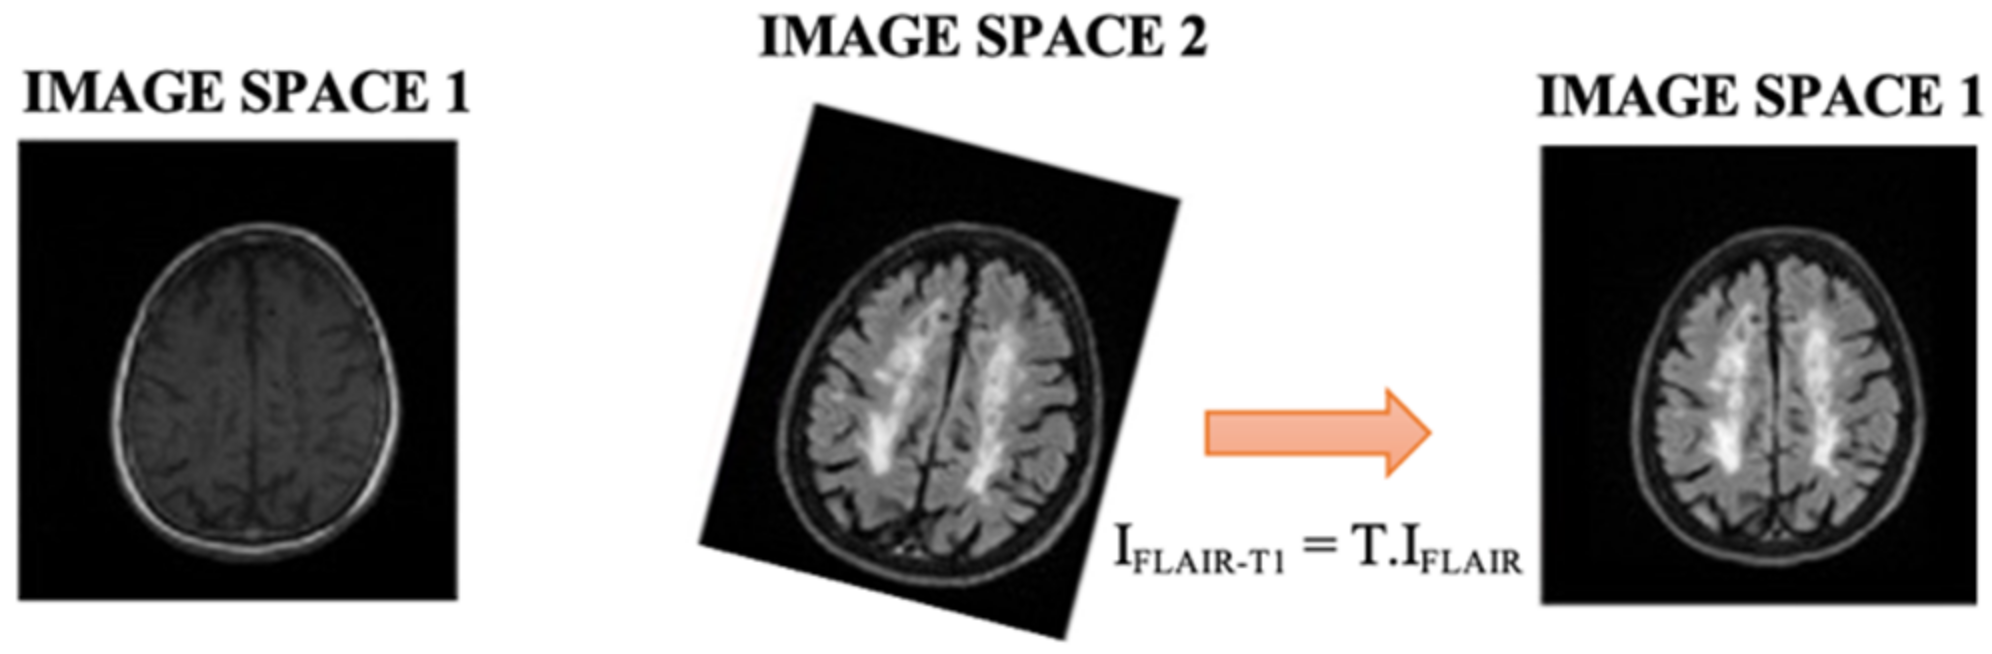

In this work, two automated methods for segmentation of brain (skull-stripper) and white matter lesions were applied to determine brain lesion volume in individuals with MS from a private test group. MRIs with T1-w and FLAIR modalities were used for the analysis, which were first preprocessed. The first step of the image preprocessing was to transform the original size images (0.43 × 0.43 × 4.5 mm3 to FLAIR and 0.47 × 0.47 × 4.5 mm3 to T1-w) to the axial 1 mm3. We then reduced the noise in the second step. Subsequently, the FLAIR slices were aligned with the T1-w slices. By applying the registration transform T to the FLAIR initial volume (IFLAIR), we generated a new volume spatially aligned with the T1-w volume (IFLAIR-T1), see Figure 3.

Figure 3.

FLAIR volume spatially aligned to T1-w volume.